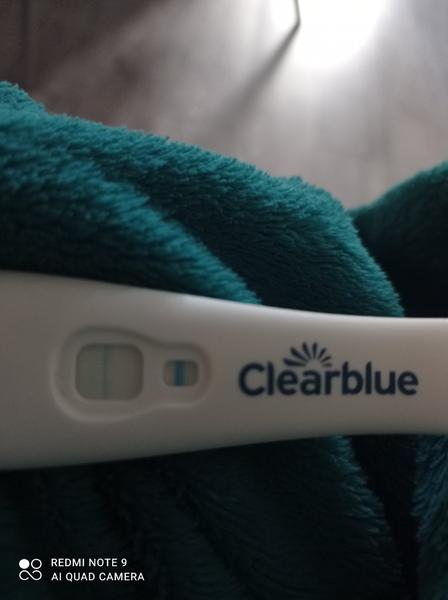

Treba skúsiť iný test pozajtra ráno. Toto je Mamatest a keby tam aj bola naznačená čiarka, pravdepodobne iba falošne pozitívna.

Tak nič dostala som to.

Nie je tam ani duch ani kanalik